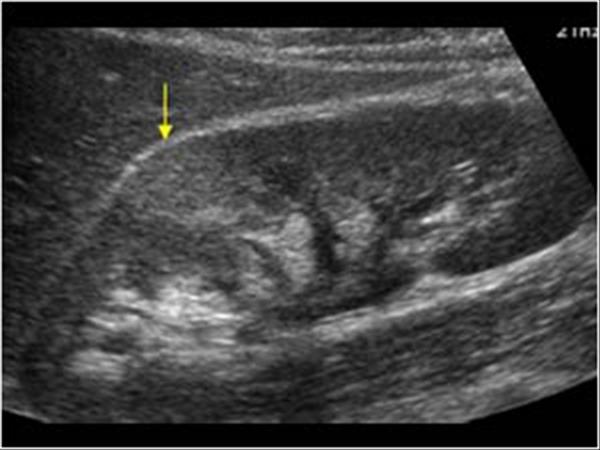

9. kép:

Vese gyulladás

A képen a nyíllal jelzett területnek megfelelően lehet látni egy elmosódott szélű világosabb területet, amely gyulladásra utal.